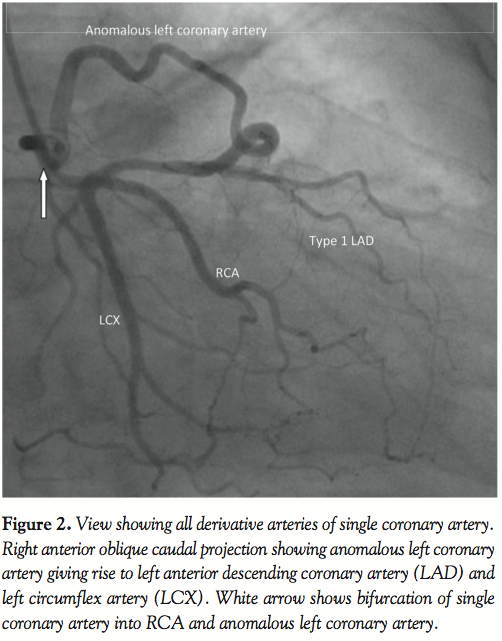

A 59-year-old man with a history of hypertension, family history of premature coronary artery disease and atypical chest heaviness was referred to exercise stress test. After achieving 89% target heart rate at a workload of 9 metabolic equivalents using Bruce protocol, 1–1.5 mm horizontal ST depressions were seen in the lateral leads. Coronary angiogram revealed a single coronary artery originating from the right sinus of Valsalva; this artery bifurcated into a right coronary artery and an anomalous left main coronary artery. Multi-detector row computed tomography confirmed the same findings. The anomalous left coronary artery followed a pre-pulmonary course anterior to the pulmonary trunk to supply the anterior descending, diagonals and circumflex artery. There was no evidence of an inter-arterial course, which is considered malignant. The coronary arteries were free of atherosclerotic disease. Stress myocardial perfusion imaging showed no inducible ischemia. Echocardiogram showed normal left ventricular function.

The overall incidence of single coronary artery disease in a series of consecutive angiograms is between 0.024%1 and 0.044%.2 An aberrant left main artery arising from a single coronary artery from the right sinus of Valsalva (R-II-A as per modified Lipton classification) was seen in 4 cases out of a series of 50,000 angiograms.3